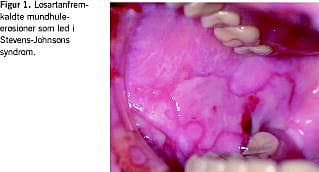

En 86-årig mand med mangeårig hypertension blev indlagt med påvirkede nyreparametre, dehydrering og kompromitteret fødeindtagelse sekundært til en svær erosiv stomatitis. Tre måneder tidligere var hans igangværende antihypertensive behandling med enalapril ændret til losartan 50 mg dagligt, mens han fortsatte en mangeårig lavdosis Magnyl-behandling. På daværende tidspunkt var nyretallene normale med serum (S)-kreatinin på 115 mikromol/l og S-karbamid på 6,4 mmol/l. Tre uger før indlæggelsen blev han febril med almen utilpashed, og få dage før indlæggelsen fik han slimhindeforandringer i næse og mundhule samt hudirritation genitalt. På mistanke om infektion indledte egen læge behandling med nystatinmundskylning og penicillin. Blodprøver viste forhøjet S-kreatinin på 183 mikromol/l og S-karbamid på 15,1 mmol/l. Ved indlæggelsen blev der konstateret svære mundhuleforandringer, og man havde mistanke om herpetisk gingivostomatitis, hvorfor penicillin blev erstattet med aciclovir, mens den igangværende lokalbehandling med nystatin fortsatte. Podning fra mundhule og svælg var negativ for herpes, candida og patogene bakterier. Tilstanden progredierede med fremkomst af fibrinbelagte og letblødende erosioner i kindslimhinderne (Figur 1 ) og ganen samt hæmoragisk skorpedannelse på prolabiet, hvilket gav mistanke om Stevens-Johnsons syndrom eller pemfigus. Anogenitalt var huden ukarakteristisk inflammeret med rødme og ødem. På begge crura var der flere purpuriske papler. Der blev iværksat behandling med lokalsteroid gruppe III. På mistanke om medikamentel udløst SJS blev losartan seponeret. Efter ni dage svandt hudforandringerne på crura, mens slimhindeforandringerne var væk efter to uger.